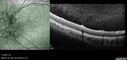

Bullous Retinoschisis - Asymptomatic54 viewsDec 17, 2025

Bullous Retinoschisis - Asymptomatic61 viewsDec 17, 2025

Bullous Retinoschisis - Asymptomatic57 viewsDec 17, 2025